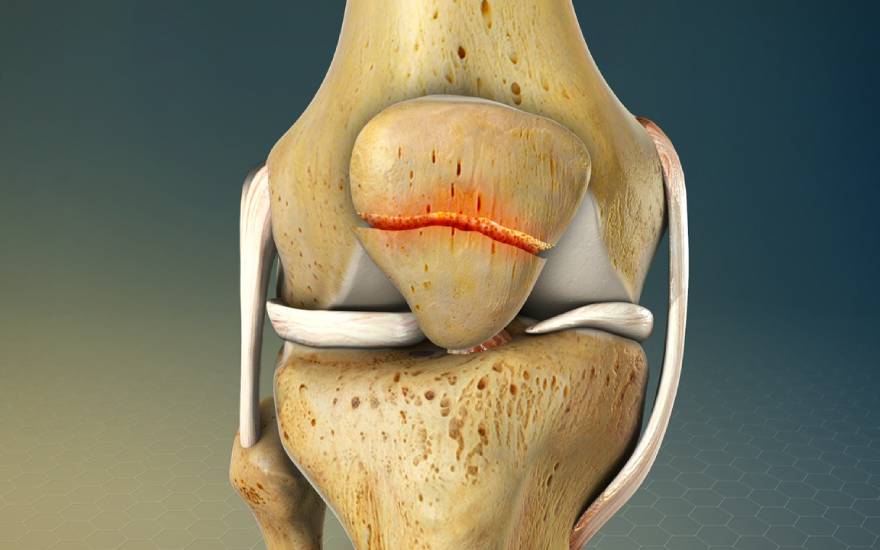

手术复位内固定

在髌骨严重粉碎、明显移位或出现游离骨块的情况下,手术治疗是更为有效的选择。医生会通过骨折复位内固定手术,将分离的骨折块重新对位并牢固固定,以恢复髌骨的正常结构和功能,从而降低日后发生关节错位或活动功能障碍等并发症的风险。

.jpg)

严重髌骨骨折通常需要通过手术进行骨折内固定治疗